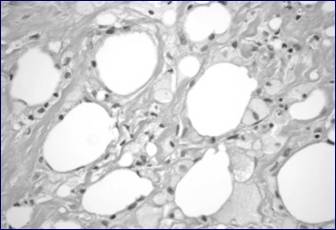

Figure 5

This photomicrograph shows tissue from the breast cavity. Note the foamy macrophages digesting dead adipocytes, indicating fat necrosis. The spaces between fat globules are filled by fibrosis.

Pathological Considerations

One of our patients (Case 1) presented with a well-developed region of fat necrosis with cavity formation. Fat necrosis is an important diagnostic consideration as it may persist and can clinically mimic carcinoma. Early in its development, fat necrosis is composed of disrupted fat cells and hemorrhage with an influx of histiocytes, some becoming multinucleate as they ingest debris. After several weeks the affected area develops peripheral fibrosis, often with calcification and forming a tumor-like lesion which may clinically mimic carcinoma (15). Attachment to the skin, dimpling and retraction are often evident. Central cystic degeneration may also occur with resultant cavity formation. This type of fat necrosis differs from fat necrosis caused by electrocautery. Electrocautery has evident thermal effect around the edges and involved areas and does not cause such extensive destruction beyond the local tissue perimeter, with several centimeters of fat necrosis, as in the case of our patient.